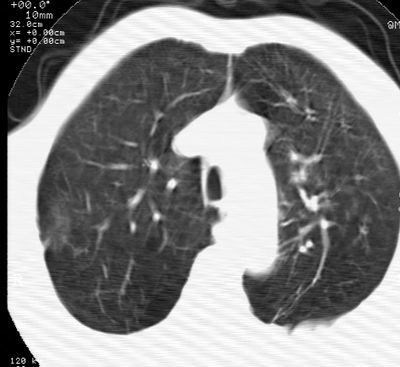

标题: CT24000:M65,胸痛,胸闷月余,既往慢支,肺气肿,肺心病 [打印本页]

标题: CT24000:M65,胸痛,胸闷月余,既往慢支,肺气肿,肺心病

左肺门肿块,相应支气管闭塞,左肺上叶、舌叶大片及散在高密度影,部分呈不张改变,两肺纹粗乱,左侧胸腔积液。考虑左侧中央型肺癌伴阻塞性改变。

左肺门见巨大软组织肿块影,直径约--,境界清,左上肺叶支气管变窄,左上肺舌叶见大片状密实影,余肺纹理增多、紊乱、纤细、部分网格状,两肺透亮度增高,纵隔内见增大多发淋巴结影,心影略左偏,左侧少量胸腔积液。

左侧中央型肺癌伴左上肺舌叶不张、纵隔淋巴结转移,左侧少量胸腔积液。